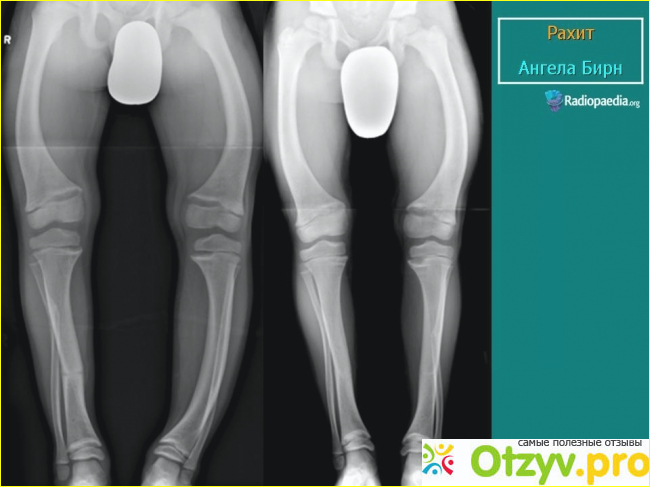

Плохое развитие, истончение костей

Витамин D участвует в развитии костей, суставов, их правильном функционировании. Поэтому очень важно обеспечить его достаточное количество для детей. Дефицит необходимого витамина может вызвать суставную, мышечную усталость, боли в спине.